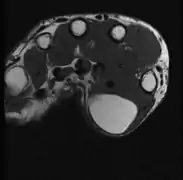

T1 MRI لنفس الورم الشحمي: كتلة إشارة عالية الكثافة مع مناطق ذات هوامش غير محددة بدقة. [13]